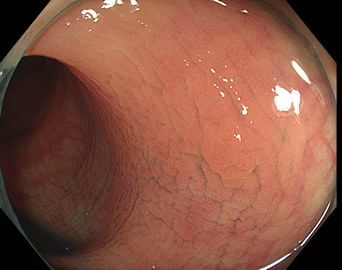

写真だけ、見ると「言われてみるとTXIの方が認識しやすい。でも僅かの差」と感じるでしょうが、この「僅かの差」が、人間の脳での検出には大きな差になります。青い色素(インジゴ・カルミン)が非常に強調され、粘膜の凸凹が明瞭になるのが特徴です。

通常観察 TXIモード

青い色素は追加していません![]()

特に、下のような「Ub型(全く凸凹の無い完全に平坦な病変)」は、以前は「ほとんど見つからなかった」のが、TXIを使うようになってから「日常的に」見つかるようになりました。